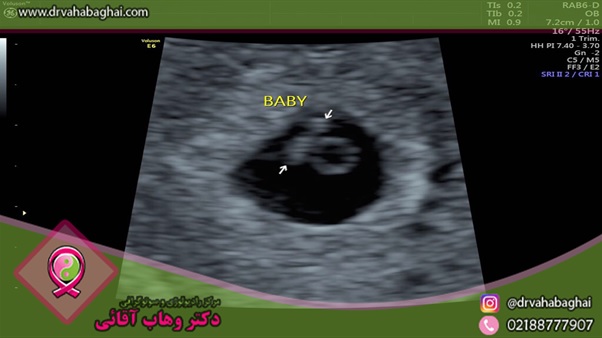

انجام سونوگرافی شکمی در بارداری از رایج‌ترین مواردی است که بانوان آن را تجربه می‌کنند. این نوع تصویربرداری به پزشک کمک می‌کند تا هر نوع نارسایی یا ناهنجاری در جنین را تشخیص دهد. لازم به ذکر است که تعیین هزینه سونوگرافی بر اساس هدف آن تعیین می‌شود.

یکی از بی خطرترین و ساده‌ترین راه‌هایی که برای مشاهده و بررسی جنین در زنان باردار به کار می‌رود، سونوگرافی شکمی است. در سونوگرافی شکمی بارداری، سلامت جنین و مادر قابل بررسی خواهد بود.

اما گاهی با وجود اینکه سقط جنین رخ داده، مادر هنوز خونریزی یا لکه بینی مبنی بر سقط مشاهده نکرده است. در این حالت سونوگرافی شکمی کمک می‌کند تا با بررسی علائم داخلی (وضعیت ساک حاملگی، جفت و ...) سقط جنین تایید گردد.

ارزیابی سلامت مادر و جنین (یا جنین‌ها) طی سونوگرافی در هفته هفتم بارداری به خوبی قابل انجام خواهد بود. برای مثال، بارداری خارج از رحم در هفته هفتم بارداری قابل تشخیص است. همچنین، با مقایسه سن بارداری و سن جنین می‌توان وجود یا عدم وجود ناهنجاری‌ها را بررسی نمود.

با انجام سونوگرافی شکمی هفته هفتم می‌توان صدای قلب جنین را شنید و از ضربان آن مطمئن گردید. در صورتی که صدای ضربان قلب جنین شنیده نشود، سقط جنین رخ داده و باید اقدامات بعدی در اسرع وقت انجام گیرد.

یکی از دلایلی که انجام سونوگرافی شکمی هفته هفتم بارداری لازم می‌سازد، تشخیص دو قلو یا چند قلو بودن آنها و تعداد کیسه حاملگی است.